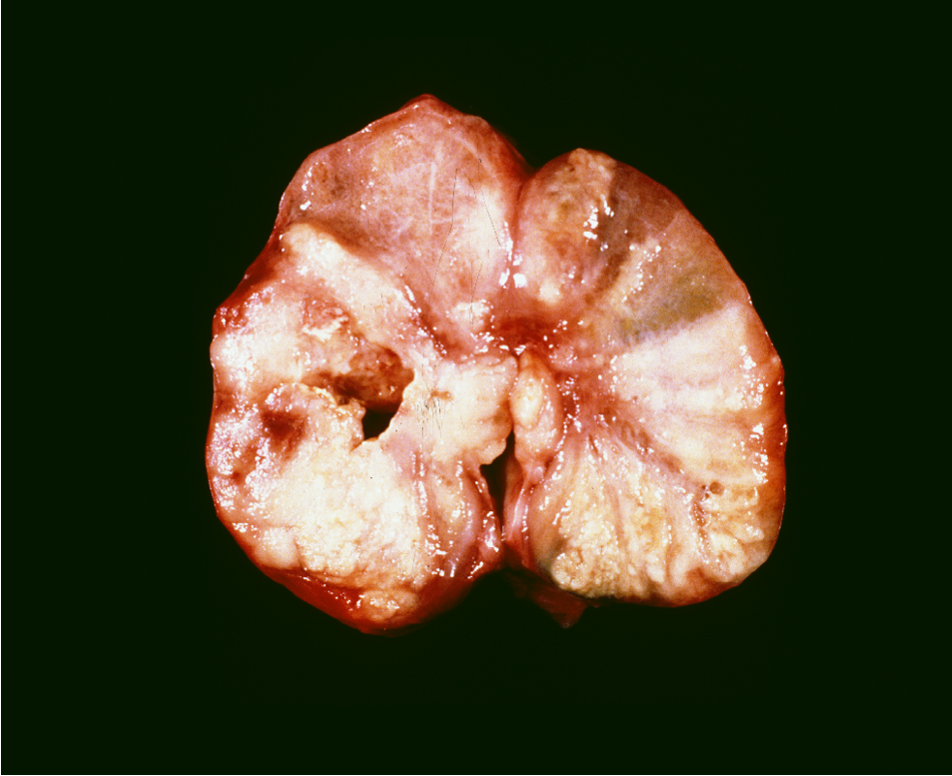

What tumours it this?

Gross: cysts, haemorrhage, yellow orange

Hx: haemorrhage, vacuolation (because steroid producting which presents as lipid)